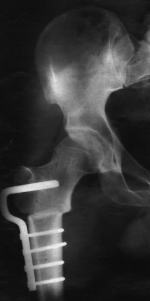

Kl: Ich betrachte mir jetzt sein Bein, sein rechtes Bein. Und zwar hat er das Bein gebrochen und das ist verschraubt ... und jetzt sehe ich ganz deutlich diese Schrauben, wie die durch diese zwei Knochen gehen, das sind vier Schrauben.

Kl: Ja, doch, das sehe ich. Ich sehe jetzt auch genau, daß sich neues Knochengewebe, oder wie man da sagt, bildet. Also, diese Bruchstelle, die ist nur zusammengefügt, aber drumherum hat sich neues Knochengewebe gebildet. Also der Riß, der ist deutlich zu sehen, aber drumherum ist es richtig gefestigt und zu.